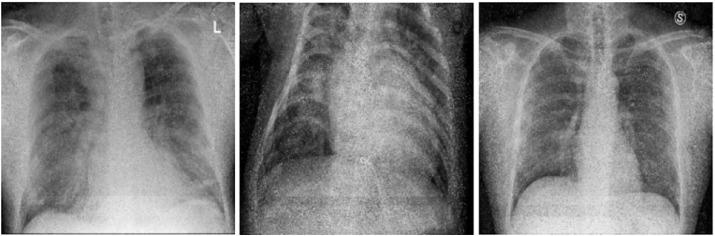

用于从胸部 X 光图像中检测 COVID-19 的轻量化深度学习模型。

Lightweight deep learning models for detecting COVID-19 from chest X-ray images.

Deep learning methods have already enjoyed an unprecedented success in medical imaging problems. Similar success has been evidenced when it comes to the detection of COVID-19 from medical images, therefore deep learning approaches are considered good candidates for detecting this disease, in collaboration with radiologists and/or physicians. In this paper, we propose a new approach to detect COVID-19 via exploiting a conditional generative adversarial network to generate synthetic images for augmenting the limited amount of data available. Additionally, we propose two deep learning models following a lightweight architecture, commensurating with the overall amount of data available. Our experiments focused on both binary classification for COVID-19 vs Normal cases and multi-classification that includes a third class for bacterial pneumonia. Our models achieved a competitive performance compared to other studies in literature and also a ResNet8 model. Our best performing binary model achieved 98.7% accuracy, 100% sensitivity and 98.3% specificity, while our three-class model achieved 98.3% accuracy, 99.3% sensitivity and 98.1% specificity. Moreover, via adopting a testing protocol proposed in literature, our models proved to be more robust and reliable in COVID-19 detection than a baseline ResNet8, making them good candidates for detecting COVID-19 from posteroanterior chest X-ray images.

深度学习方法在医学影像问题中已经取得了前所未有的成功。在从医学图像中检测 COVID-19 方面,也取得了类似的成功,因此深度学习方法被认为是与放射科医生和/或医生合作检测这种疾病的良好候选方法。在本文中,我们提出了一种新的方法,通过利用条件生成对抗网络来生成合成图像来增强可用的有限数量的数据,从而检测 COVID-19。此外,我们还提出了两种遵循轻量级架构的深度学习模型,与可用数据的总量相匹配。我们的实验重点是 COVID-19 与正常病例的二进制分类以及包括细菌性肺炎的第三类的多分类。与文献中的其他研究相比,我们的模型也与 ResNet8 模型相比,表现出了有竞争力的性能。我们表现最好的二进制模型达到了 98.7%的准确率、100%的敏感性和 98.3%的特异性,而我们的三分类模型达到了 98.3%的准确率、99.3%的敏感性和 98.1%的特异性。此外,通过采用文献中提出的测试方案,我们的模型在 COVID-19 检测方面比基线 ResNet8 更稳健和可靠,使它们成为从前后位胸部 X 光图像中检测 COVID-19 的良好候选方法。